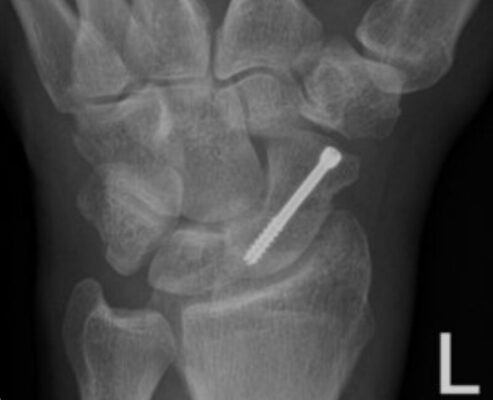

Đối với các gãy xương không di lệch hoặc di lệch tối thiểu, cố định qua da bằng vít đã trở thành phương pháp điều trị được chấp nhận. Một phân tích tổng hợp gần đây đã báo cáo rằng việc cố định qua da có thể dẫn đến sự liền xương sớm hơn 5 tuần so với điều trị bó bột và trở lại chơi thể thao hoặc làm việc sớm hơn khoảng 7 tuần so với điều trị bó bột (Modi và cộng sự 2009).

Sau phẫu thuật, cổ tay thường được cố định ban đầu ở nẹp bột và sau đó được bó bột hoàn toàn sau hai tuần sau khi xem lại vết thương và chụp lại phim X quang. Cổ tay được bó bột hoàn toàn cho đến sáu tuần sau phẫu thuật, và lặp lại phim chụp X quang và tháo bột nếu có dấu hiệu X quang của xương đang lành. Bệnh nhân có thể cần phải mang thêm nẹp cổ tay trong sáu tuần nữa để bảo vệ cổ tay.